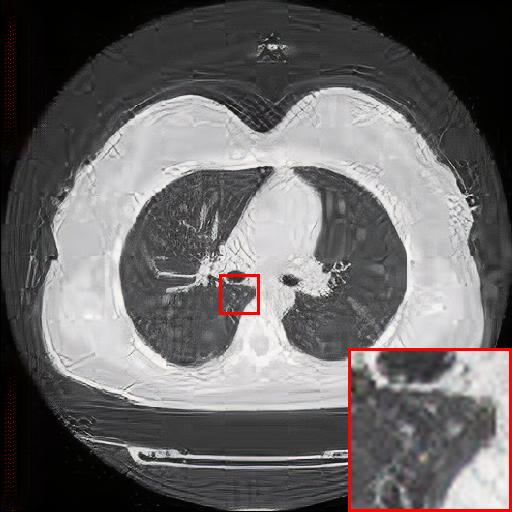

Figure 5: Reconstruction results of each algorithm for low-doze chest CT images.

III-D Super-resolution Reconstruction of Low-dose CT images

Medical pictures, such as computed tomography (CT) scans, are widely used in clinical applications such as noninvasive illness detection, anatomical imaging, and treatment planning, all of which need judgment while doing CT scans. These imaging approaches, however, have some drawbacks. During CT scans, for example, radiation damage is unavoidable. Low-dose CT (LDCT) is currently the clinically recommended strategy for preventing irreversible radiation harm to the body, however it comes at the cost of getting CT pictures with low resolution or noise contamination. The spatial resolution is generally coarser than that of CT imaging in order to get images with a high signal-to-noise ratio. As a result, obtaining high-resolution scanned images with a low-dose CT scanner is now a challenge.

In this section, we selected chest CT images of COVID-19 patients in an actual hospital [26] for our experiments. The visualization results of the experiments are shown in Figure 5 and Figure 6. The experimental results show that our proposed T-GAN is also applicable to the super-resolution reconstruction of low-dose CT images, and the high-resolution images obtained by our model have more detailed information compared with the baseline algorithm.